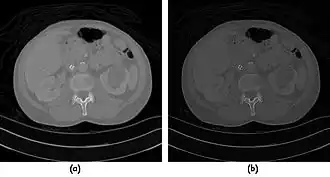

- A choice of filters can generally be selected to enhance either soft tissue features in the image or bone detail. Indeed, the image can be post-processed using a different filter after the scan has been completed if needed. Images can be generated to enhance bone detail or display subtle low contrast masses without the need to re-scan the patient. The filter choice therefore has a major impact on image quality. The two most common filters used in X-ray CT are those due to Ramachandran & Lakshminarayana (commonly called the Ram-Lak) and Shepp & Logan. Viewed in spatial frequency space, the former is essentially a ramp filter with a cut off frequency and the latter combines a smoothing filter with the ramp to attenuate high frequency noise. The ramp filter compensates for the artefacts introduced by the simple back projection process but does not compensate for the increasing noise content of the data with increasing frequency. Images of an axial tomogram reconstructed with a soft tissue and with a bone algorithm can be seen in Figure 7.14.

![]() |

- Examples of image display manipulation are shown in the two figures above. In Figure 7.15.2, the same image of a slice through a patient's liver is displayed using a relatively narrow window (high contrast) and also with a wide window. The image with the narrower window appears noisier, but this is merely a reflection of the fact that the gray scale is spread over a narrow range of CT-numbers.

- Figure 7.15.3 illustrates the use of a relatively narrow window to highlight pathology in the lungs.